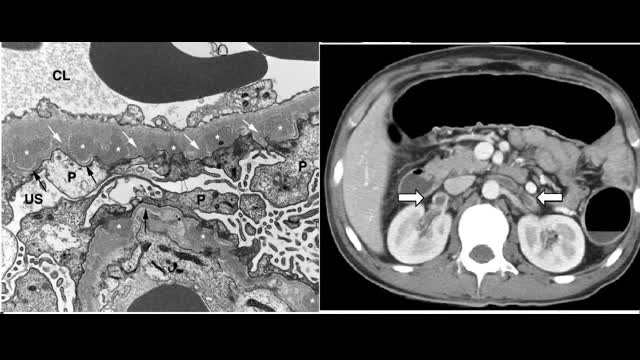

48-year-old man presents with acute onset right flank pain and nephrotic syndrome